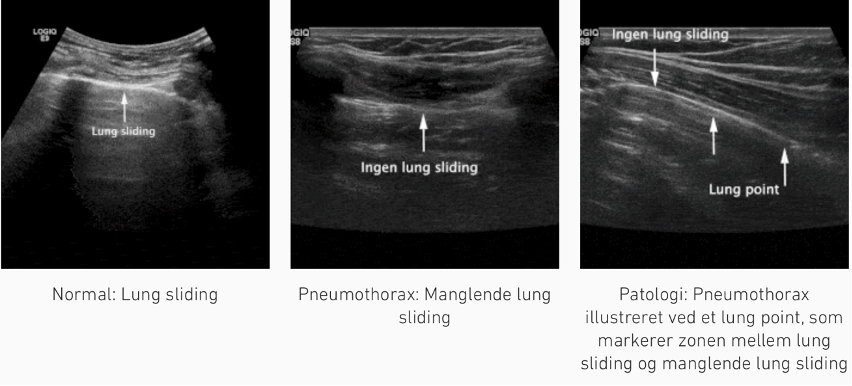

Zone 1 og 2 (Hemithorax anteriort [højre + venstre]): 1

1: pneumothorax eller pleuraansamling